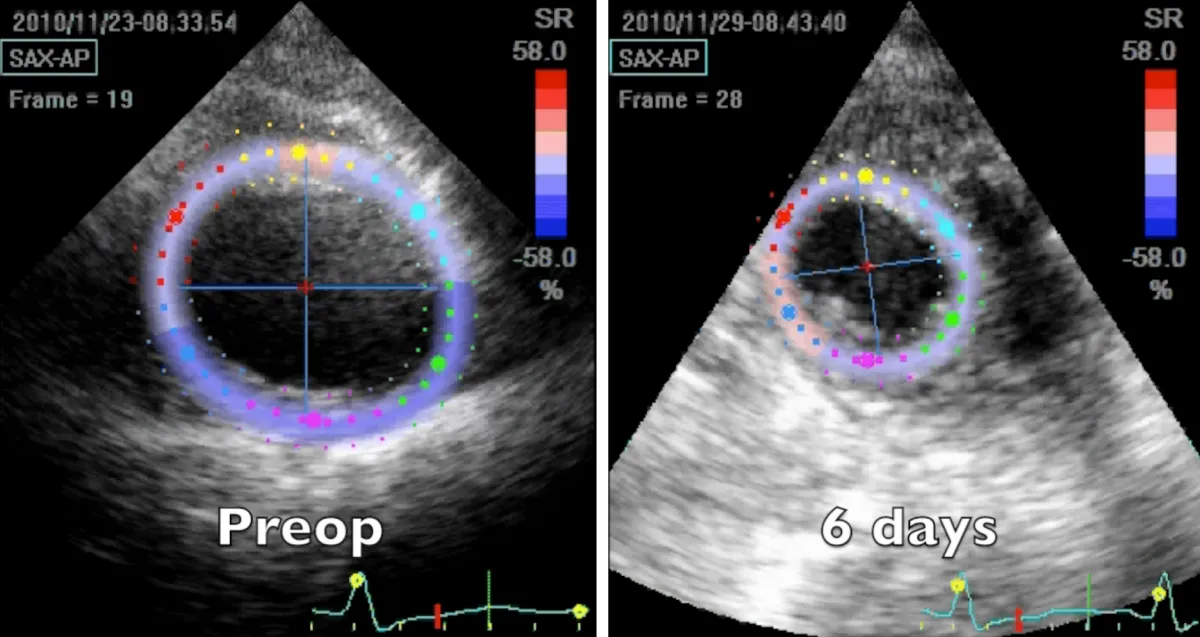

Figure 4: 2D speckle tracking echocardiography short axis apical systolic frames at two controls, preoperative and 6 days after the operation.

Video 5: Echocardiography apical short axis view; comparison between preoperative and 6 days after the operation controls. Note the abnormal clockwise rotation of the preoperative dilated apex and its near normal functional counter clockwise rotation few days after the surgical correction.

Apical region study (Figure 4 and Video 5) clearly demonstrates an improvement in apical geometry and rotation (from - 4.1 degrees to 4.6 degrees) in the immediate postoperative period induced by the surgically reoriented bundles of fibers. Consequently, left ventricular torsion improved to 7 degrees after the operation, with a reduction to about 4 degrees four years after surgery, due to a new-onset small apical dyskinetic area that reduces counterclockwise rotation to 1.3 degrees. Magnetic resonance short axis views (Figure 3 and Video 4) highlight the physiologically restored left ventricle along its whole length, from the apex to the base. The key surgical steps of this technique are: a) the septal rim of the suture is as long as the patch; b) the lateral rim of the suture shrinks the displaced fibers to a more physiologic orientation, given that it must adapt the dilated lateral wall onto the patch; c) a new apex is rebuilt (elliptic shape); d) a very small “akinetic” patch is used to bring closer the normal myocardium, redirecting fibers in a more physiologic disposition (Video 6).